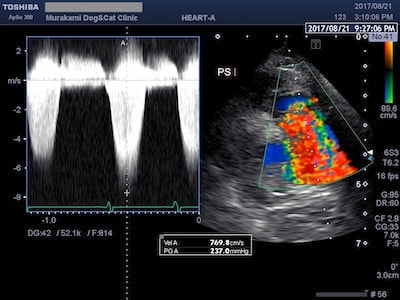

肺動脈狭窄症(PS)

肺動脈狭窄症(PS)は、犬の先天性心疾患の中ではPDAに次いで多い疾患です。狭窄部位により弁性狭窄、弁下狭窄、弁上狭窄に大別されます。犬では弁性狭窄が多くみられ、その重症度によっては突然死の原因となるため、外科的に狭窄部位を拡張する必要があります。

SAMによる左室流出路閉塞

異常な動きをする僧帽弁により左室流出路閉塞が起こると、左心室から流出する血流(大動脈血流)に高速血流が生じます(ホースの先端を摘むと水が勢いよく出るイメージ)。SAMの場合は左室流出血流波形がダガーシェイプ(ダガーナイフ型)になるのが特徴です。治療には左室流出路閉塞を緩和する目的で心拍数を抑えるお薬を使います。